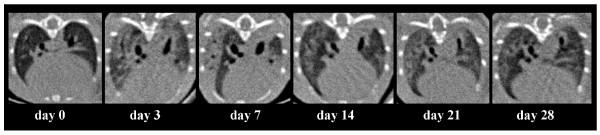

Survival studies, computed tomographic scanning, histology, bronchoalveolar lavage were performed, and arterial blood gases and hemodynamics were measured in animals which received an intravenous injection of different doses of monocrotaline pyrrole.

Monocrotaline pyrrole induced pulmonary hypertension in Sprague Dawley rats. When injected into mice, monocrotaline pyrrole induced dose-dependant mortality in C57Bl6/N and BALB/c mice (dose range 6-15 mg/kg bodyweight). At a dose of 10 mg/kg bodyweight, mice developed a typical early-phase acute lung injury, characterized by lung edema, neutrophil influx, hypoxemia and reduced lung compliance. In the late phase, monocrotaline pyrrole injection resulted in limited lung fibrosis and no obvious pulmonary hypertension.

方法

野百合碱吡咯可诱导Sprague Dawley大鼠发生肺动脉高压。当注射到小鼠体内时,野百合碱吡咯在C57Bl6/N和BALB/c小鼠中诱导剂量依赖性死亡(剂量范围为6-15mg/kg体重)。在10mg/kg体重的剂量下,小鼠出现典型的早期急性肺损伤,其特征为肺水肿、中性粒细胞浸润、低氧血症和肺顺应性降低。在后期,注射野百合碱吡咯导致有限的肺纤维化,且无明显的肺动脉高压。